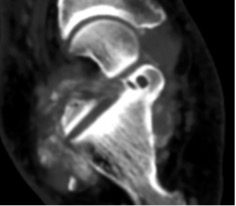

COMPUTED TOMOGRAPHY (CT)

CT demonstrating subtalar joint non-union

Generation of CT image

The patient lies on the CT table and is moved slowly through the centre of a circular gantry containing a rotating X-ray generator and detectors. The narrow X-ray beams are absorbed or attenuated to various degrees depending on the density of the tissues being imaged.

The remaining unabsorbed or unattenuated X-rays pass through the tissue and are picked up by an array of detectors and processed by a computer. The CT software converts the beam attenuations of the tissue into an image which is digitised into a visual display.

Tissues with high attenuation (e.g. cortical bone) appear white; tissues with low attenuation (e.g. air) appears black; soft tissues with intermediate attenuation are variations of grey.

Usually 1.5 - 2mm contiguous axial sections are obtained through the foot and ankle which can be used to create multiplanar sagittal and coronal reformats as well as three-dimensional reconstructions.

Indications

The main use of CT is for the identification of bone-based pathology due to the excellent bone detail generated.

Fractures – fracture characterisation, intra-articular extension, fracture fragments, fracture union. Multiplanar reconstructions are helpful in pre-operative planning.

Bone lesions – lesion characterisation (matrix calcification, nidus of osteoid osteoma, stress fracture), intra-osseous extent, cortical breach, CT-guided biopsy or other (radiofrequency ablation, sclerotherapy).

Other specific bone and joint pathology – stress fractures, coalitions, osteochondral defects, loose ossific bodies.

Post-operative assessment – union of fusions, metalwork, alignment.